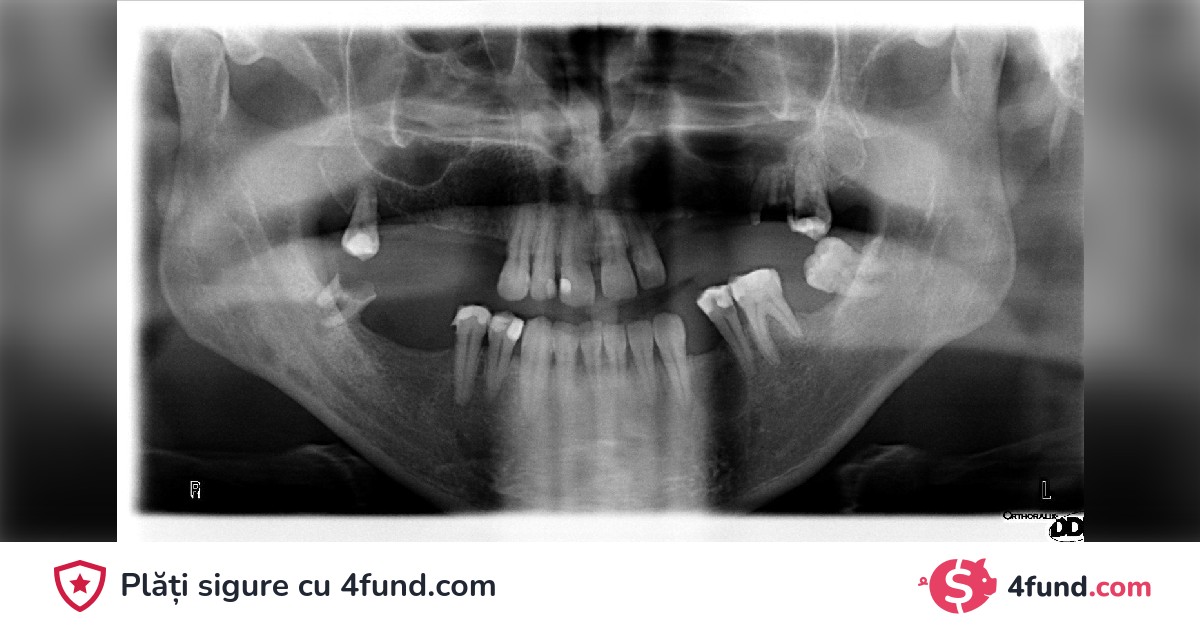

Over the years, I have faced oral health challenges that have made my life a journey of pain and embarrassment. Dental problems have not only affected my self-esteem but also my overall health, becoming a daily battle that I cannot win alone.

As far back as I can remember, I have had issues with my teeth. Unfortunately, due to financial limitations, postponing treatment was my only option. This delay has caused significant damage, and I now face a series of serious dental complications.

My necessary dental treatment includes surgeries, extractions, implants, and extensive dental restorations. The cost of these procedures is significant and is beyond what I can afford on my own. That is why I am turning to you, the community, and friends to help me restore my oral health and, with it, my self-esteem and quality of life.